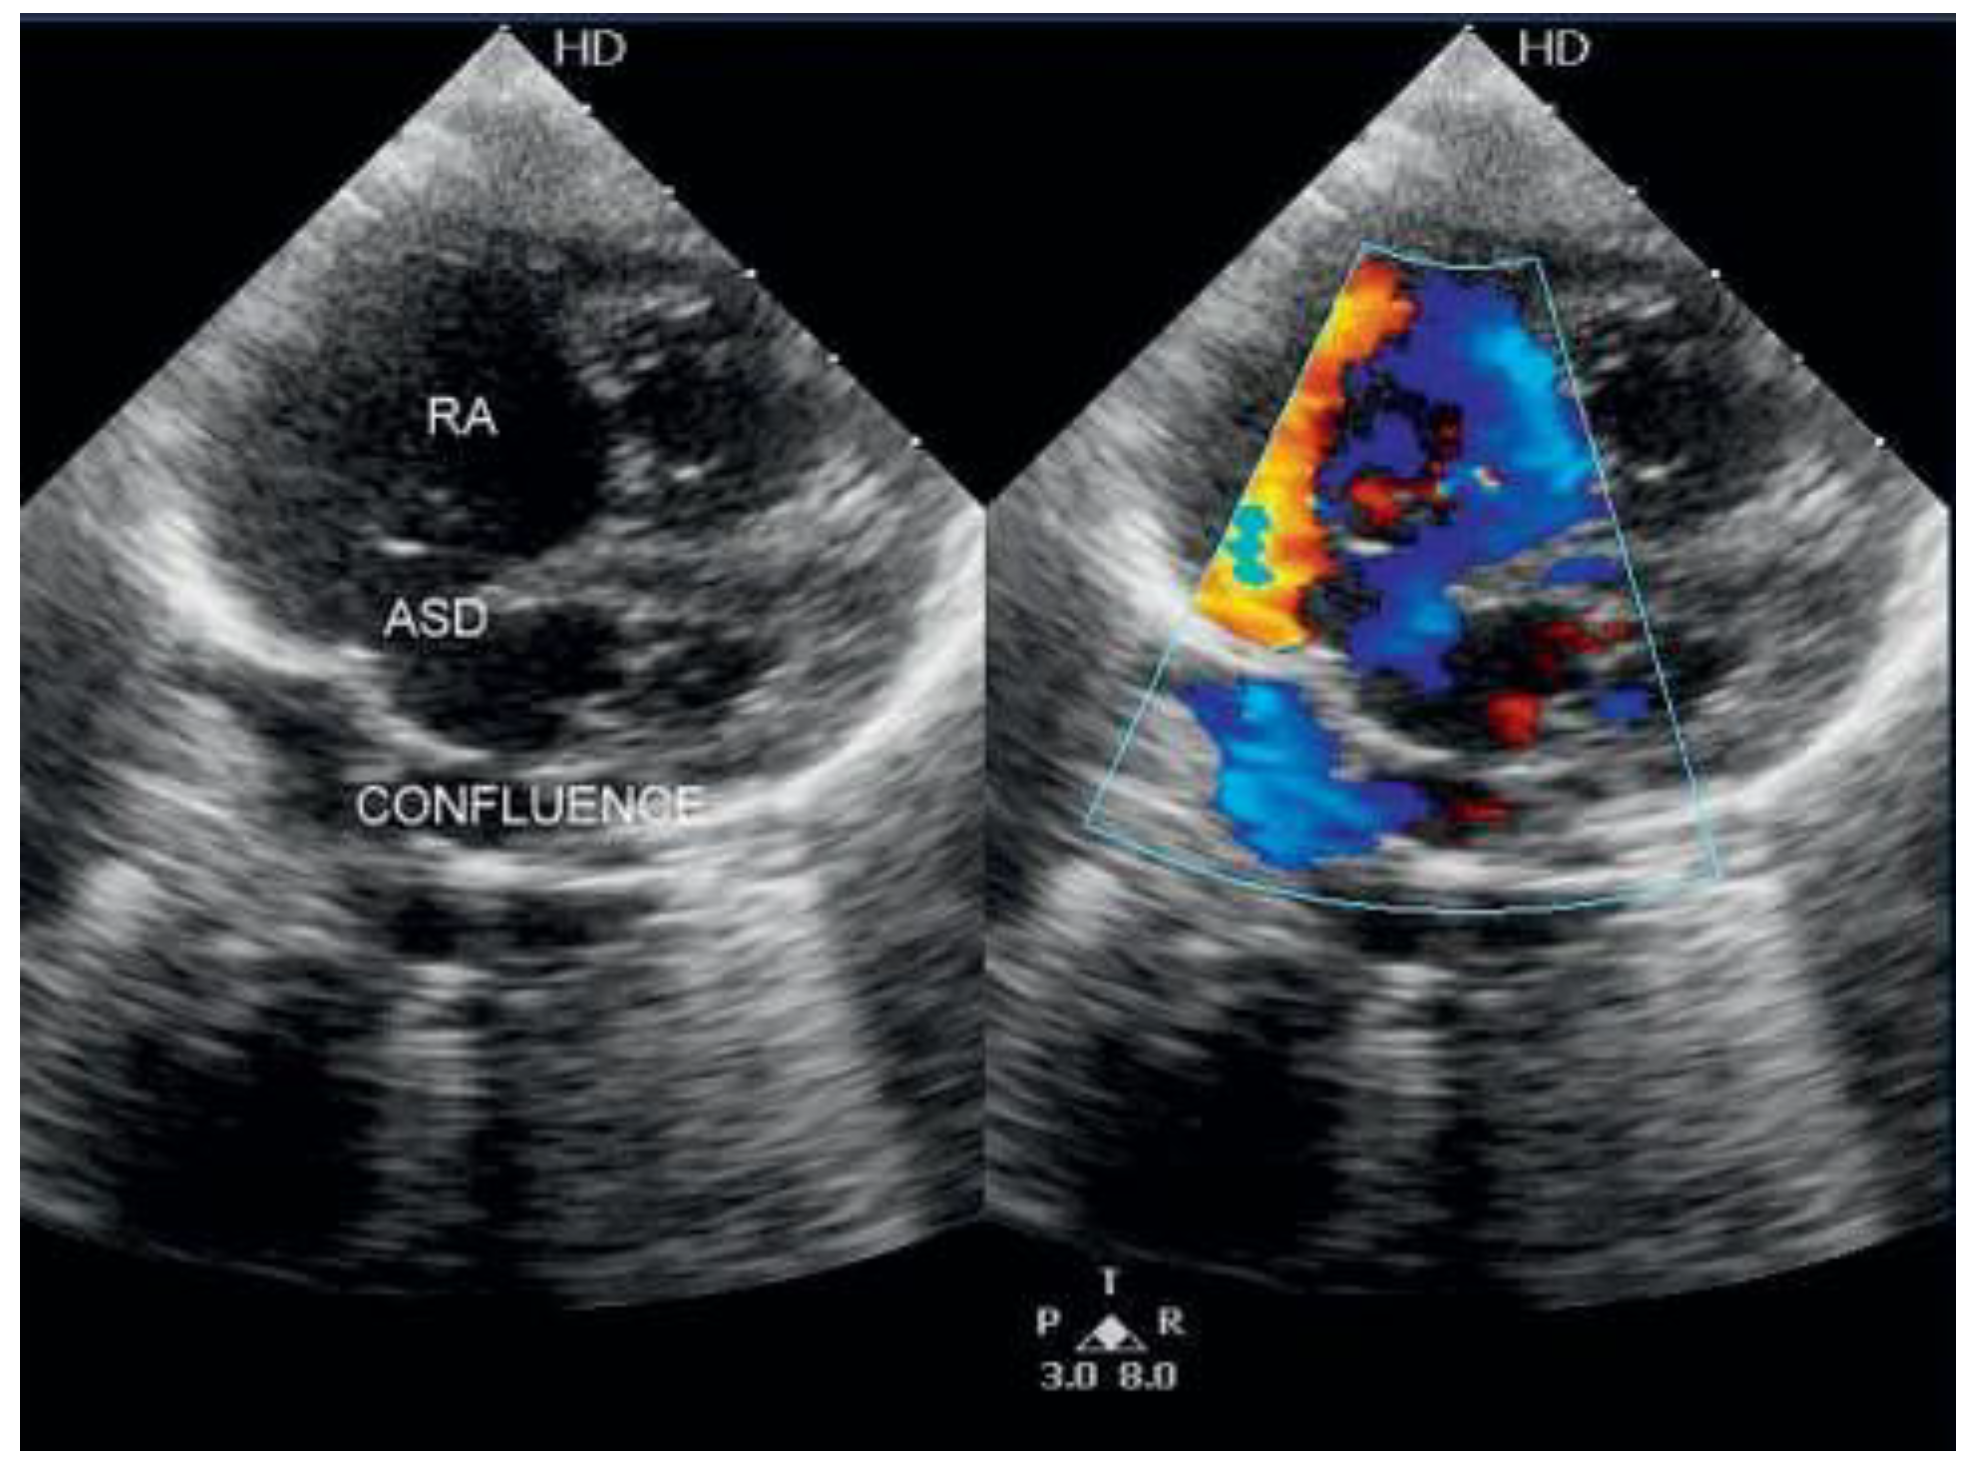

Supracardiac Total Anomalous Pulmonary Venous Connection with Right Ascending Vertical Vein

Case Report